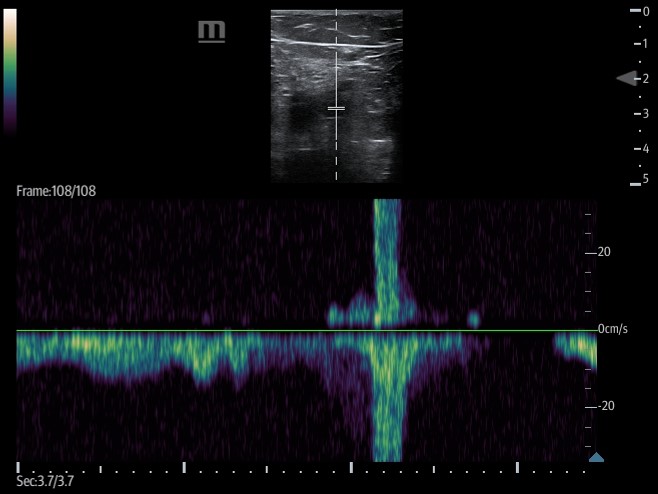

- Augmentation

- Involves placing the transducer proximally on the leg, typically at the CFV, and setting the ultrasound machine to color or pulsed wave Doppler mode.

- The calf is then squeezed or compressed along the venous system in order to increase venous return.

Video 5. Augmentation demonstrates color flow in proximal portion of vein when calf is squeezed.

- Figure 16. Pulsed wave doppler demonstrating increased venous return with augmentation.

- If no DVT is present, there will be an increase in flow velocity noted on the ultrasound machine screen once the rush of blood passes the area where the transducer is placed.

- A lack of increased flow identified may be suggestive of an occlusive thrombus between the two points.

- Partial obstruction may can dampened flow when compared to the other side but can also cause subtle change in flow which can lead to false negative augmentation study.